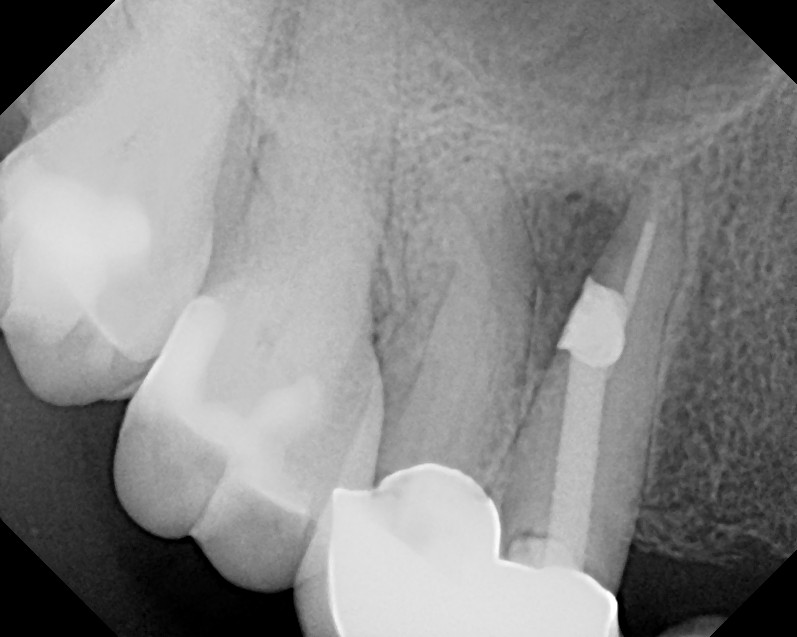

From www.theendoblog.com

The Endo Blog Root Canal Treatment Saves a Perforated Tooth What Is A Perforated Root Canal 2 to clinically determine if an endodontically perforated tooth. Once a perforation is properly diagnosed, located, and. Perforation of the pulp chamber or root walls during instrumentation of root canals exposes the supporting tissues of the tooth to bacterial contamination and often leads. Root perforation is considered an unpleasant error in an operative procedure. Root perforations are communications between the. What Is A Perforated Root Canal.